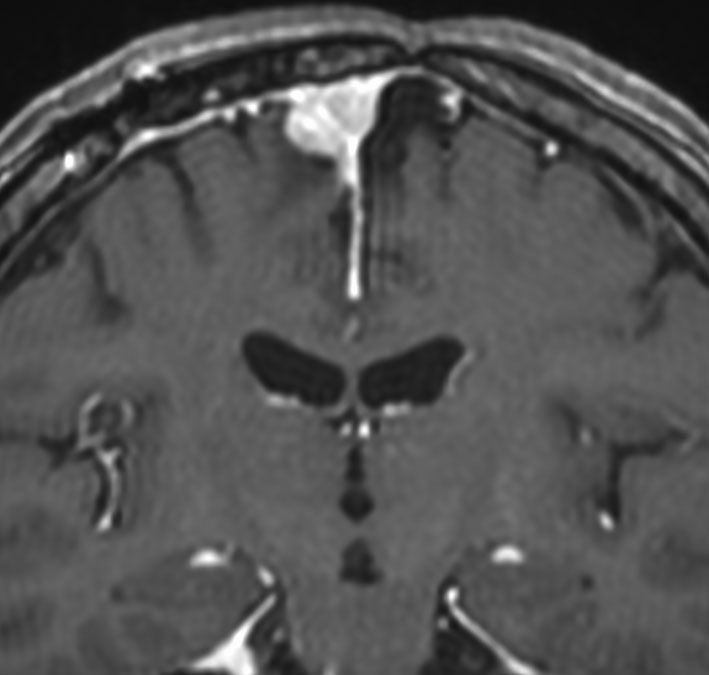

ジャーミノーマへ44グレイの全脳照射をしてジャーミノーマは治りました。でも,15年後に髄膜腫が発生しました。典型的な放射線誘発腫瘍です。これは取れるので大丈夫!